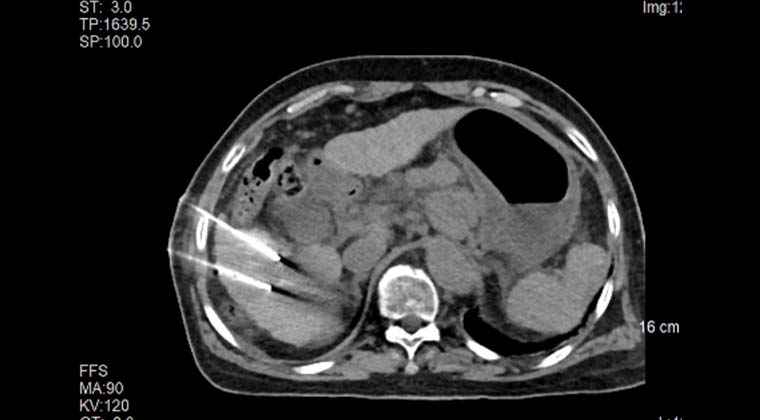

Точная чрескожная пункция опухоли под контролем интраоперационной КТ